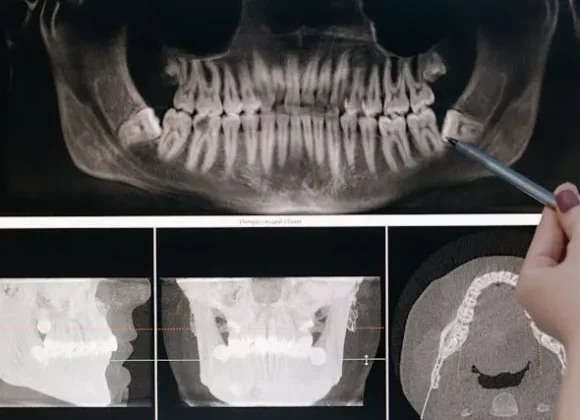

2. Use advanced imaging (like 3D CBCT scans) to evaluate your bone structure